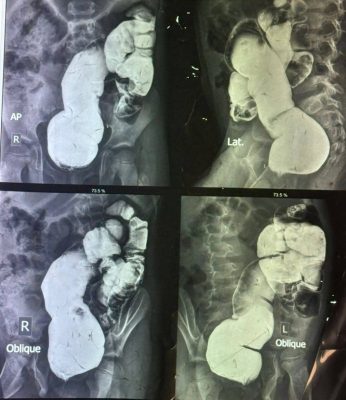

وذكر رئيس الفريق الطبي الجراحي الدكتور علي عكاب جودة : تم إجراء عملية نوعية استئصال القولون السيني مع تفويه القولون النازل لطفل يبلغ من العمر 5 سنوات كان يعاني من امساك مزمن (Dolichsigma) لم يستجب للعلاج التحفظي ، وبعد الفحص السريري والتحاليل المختبرية ، أجريت العملية الجراحية تحت التخدير العام، وتكللت العملية بالنجاح وأُخرج الطفل بعد إكتسابه للشفاء التام.